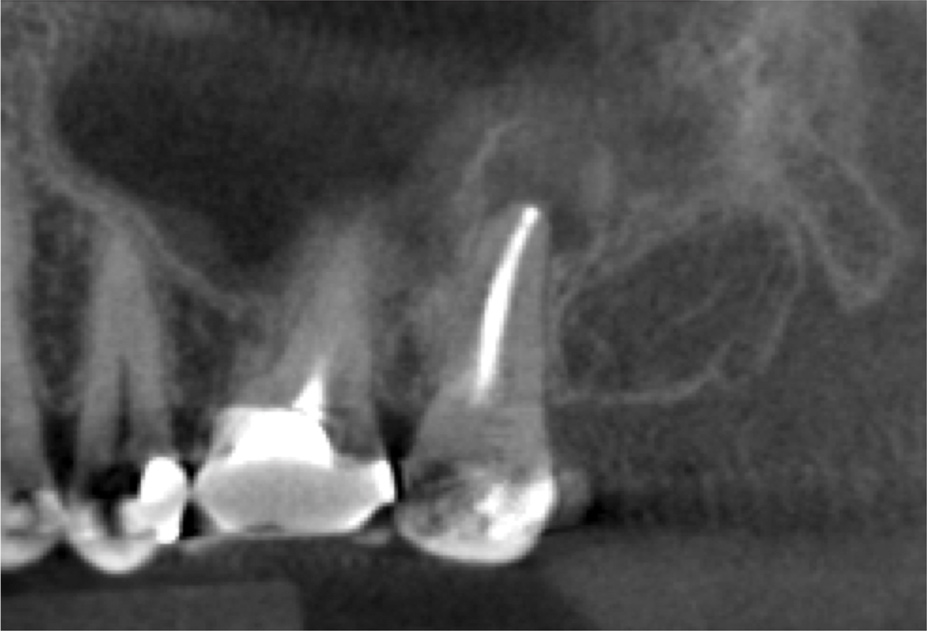

For patients suffering from MSEO, radiographs will reveal a periapical radiolucency with adjacent opacification in the maxillary sinus.12 Additional radiographic findings associated with MSEO include periapical mucositis and periapical osteoperiostitis (PAO). Periapical mucositis refers to mucosal thickening or dome-shaped soft-tissue expansion on the floor of the sinus directly adjacent to the infected root apex.PAO refers to the reactive osteogenesis caused by a local periosteal reaction that expands the sinus periosteum and displaces it upward into the sinus. It appears as a radiopaque "halo" surrounding the root apex (Figure 2 through Figure 4). PAO may be symptomatic and/or accompanied by adjacent mucosal edema and elevated sinus fluid levels.9 If left untreated, PAO can progress and result in a direct communication between the root apex and maxillary sinus.6,13 Unless bilateral odontogenic pathosis is found, the sinus opacifications will usually be unilateral and centered around the odontogenic source. Complete unilateral sinus opacifications may be missed on the CBCT images typically used in endodontics due to their limited or focused field of view (Figure 5). In cases involving complete unilateral sinus opacification, referral to an ENT or oral surgeon is essential to rule out invasive fungal infection or malignancy.2,17,24

(4.) Coronal slice of CBCT image of the same tooth.

Figure 4